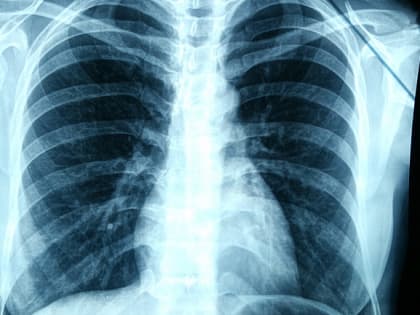

"ПОЙМАТЬ РАК": ПОЧЕМУ СТОИТ БРОСИТЬ КУРИТЬ И БЫТЬ ВНИМАТЕЛЬНЫМ К СВОИМ ЛЕГКИМ

Заведующий отделением торакальной онкологии Архангельского клинического онкодиспансера, хирург Андрей Мармуро рассказал, какие заболевания помог выявить COVID-19, с каким кашлем нужно обращаться к врачу,